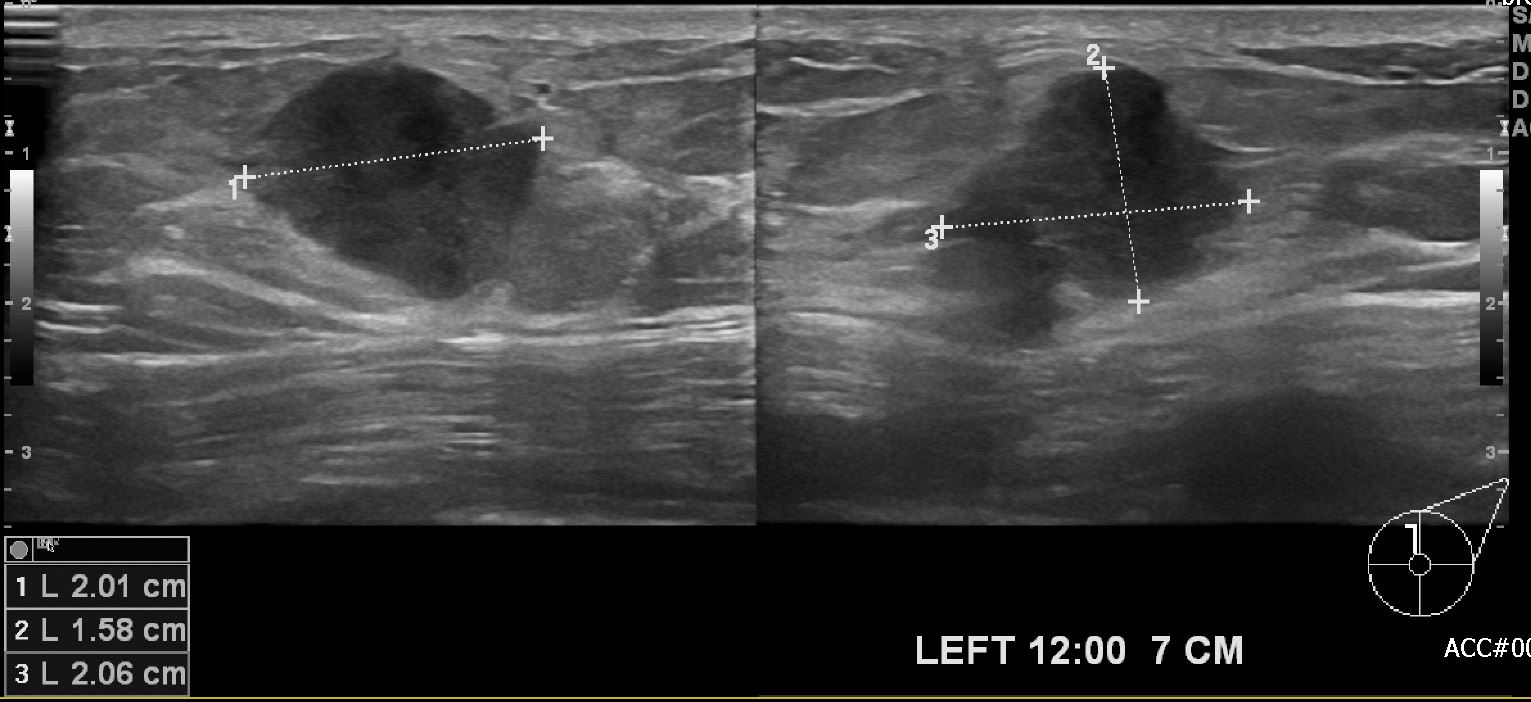

건강검진상 이상소견보여 방문하신 50대 여자환자분으로 본원에서

왼족유방 12시방향 7cm 떨어진 곳에 조직검사시행하여 왼쪽유방

침윤성유관암 진단되셨습니다.